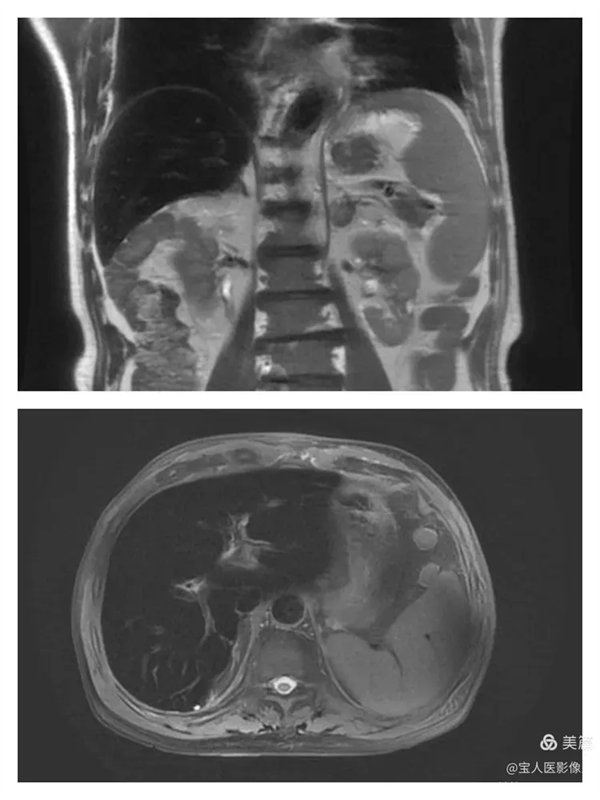

T2WI冠位,軸位,肝實質信號明顯降低,呈“”黑肝征”,而脾臟信號正常。

T1WI圖,軸位,肝實質信號仍呈明顯低信號。